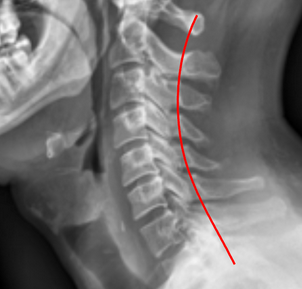

Image Type Cervical Spine X-Ray CT Scan MRI Scan Atlantodental Interval (ADI) Basion-Axial Interval Basion-Dens Interval (BDI) C2 Tilt C2–C7 Coronal Cobb Angle Cervical C2-7 lordosis C2-C7 Translation Chamberlain’s Line / McGregor’s Line Flexion-Extension George’s Line (Posterior Cervical Line) K-Line Interpedicular Distance (IPD) Occiput-C2 Angle Occipital Condyle–C1 Interval (CCI) Posterior Atlantodental Interval (PADI) Power’s ratio Sagittal Canal Diameter Sagittal Vertical Axis (SVA) Spinolaminar line Swischuk Line T1 Slope Torg/Pavlov Canal-to-Body Ratio